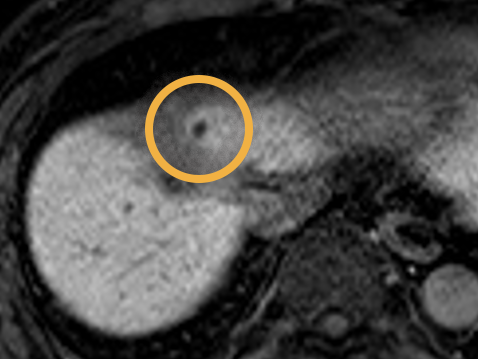

T2-weighted MRI of 0.28×10 mm Gold Anchor MR+ implanted with ball shape in prostate.

T2-weighted MRI of 0.4×10 mm Gold Anchor MR+ implanted with ball shape in prostate.